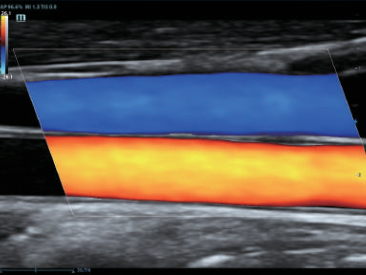

–€–Ψ–Ϋ–Ψ–Κ―Ä–Η―¹―²–Α–Μ–Μ–Η―΅–Β―¹–Κ–Η–Β –¥–Α―²―΅–Η–Κ–Η ―¹ ―²–Β―Ö–Ϋ–Ψ–Μ–Ψ–≥–Η–Β–Ι 3–Δ?

–ë–Μ–Α–≥–Ψ–¥–Α―Ä―è ―¹–Ψ―΅–Β―²–Α–Ϋ–Η―é ―²–Β―Ö–Ϋ–Ψ–Μ–Ψ–≥–Η–Η 3–Δ? (–Δ―Ä–Ψ–Ι–Ϋ–Ψ–Ι ―¹–Ψ–≥–Μ–Α―¹―É―é―â–Η–Ι ―¹–Μ–Ψ–Ι, ―²–Β―Ö–Ϋ–Ψ–Μ–Ψ–≥–Η―è –Ω–Ψ–Μ–Ϋ–Ψ―¹―²―¨―é ―Ä–Α–Ζ–¥–Β–Μ–Β–Ϋ–Ϋ―΄―Ö –Κ―Ä–Η―¹―²–Α–Μ–Μ–Ψ–≤, ―²–Β―Ä–Φ–Ψ–Κ–Ψ–Ϋ―²―Ä–Ψ–Μ―¨ –Α–Κ―É―¹―²–Η―΅–Β―¹–Κ–Ψ–Ι –Μ–Η–Ϋ–Ζ―΄) –Η –Φ–Ψ–Ϋ–Ψ–Κ―Ä–Η―¹―²–Α–Μ–Μ–Η―΅–Β―¹–Κ–Η―Ö –¥–Α―²―΅–Η–Κ–Ψ–≤ –Ψ–±–Β―¹–Ω–Β―΅–Η–≤–Α–Β―²―¹―è –Κ–Α–Κ –±–Ψ–Μ–Β–Β –≤―΄―¹–Ψ–Κ–Α―è ―Ä–Α–Ζ―Ä–Β―à–Α―é―â–Α―è, ―²–Α–Κ –Η –Ω―Ä–Ψ–Ϋ–Η–Κ–Α―é―â–Α―è ―¹–Ω–Ψ―¹–Ψ–±–Ϋ–Ψ―¹―²―¨, –≤ ―Ä–Β–Ζ―É–Μ―¨―²–Α―²–Β ―΅–Β–≥–Ψ ―Ä–Β―à–Α–Β―²―¹―è –Ω―Ä–Ψ–±–Μ–Β–Φ–Α –Η―¹―¹–Μ–Β–¥–Ψ–≤–Α–Ϋ–Η–Ι ―²–Β―Ö–Ϋ–Η―΅–Β―¹–Κ–Η ―¹–Μ–Ψ–Ε–Ϋ―΄―Ö –Ω–Α―Ü–Η–Β–Ϋ―²–Ψ–≤.